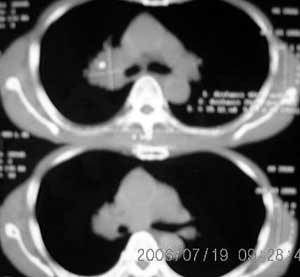

以下是引用卜一在2006-7-20 14:13:00的发言:[br]图象质量差了些,首先考虑:中心性肺癌伴阻塞性肺炎.因发生在右肺上叶尖后段,而且外带见二个空洞影,次考虑:不排除肺结核

以下是引用1983在2006-7-20 21:53:00的发言:[br]右侧中央型肺癌伴阻塞性肺炎.

以下是引用jiangjing在2006-7-20 19:22:00的发言:[br]右侧肺门见有软组织肿块,边缘不规则,不光整,其周围肺内见炎性片状影,胸片示水平裂呈弧形上移,右上叶支气管狭窄,考虑右肺中央型肺癌伴阻塞性肺炎部分肺不张。